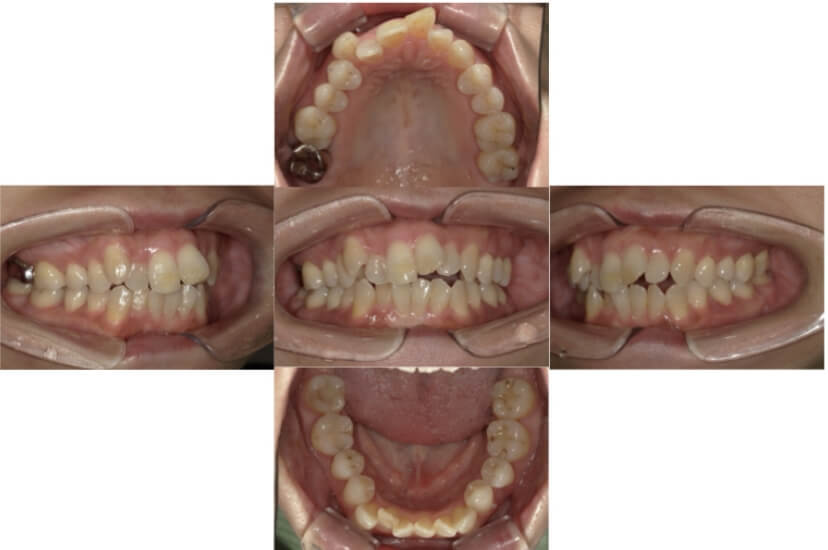

症例4

下顎前突、叢生

抜歯

ブラケット矯正

上下顎叢生、反対咬合(上下の前歯のガタガタ、若干受け口)のケースです。

装置はラビアル(上下表側)で、上下顎の小臼歯を4本抜歯を行っています。抜歯したスペースを使って、上下の叢生改善と前歯の受け口の改善を行っています。

主訴 前歯のガタガタを治したい。

年齢・性別 45歳 女性

お住まいの地域 神奈川県川崎市

治療方針 抜歯スペースを利用して上前歯の叢生(ガタガタ)の改善と受け口の改善

抜歯部位 上顎左右第一小臼歯、下顎左右第二小臼歯

使用装置 ラビアル(上下表側)、顎間ゴム

治療期間 2年6か月

治療回数 20回

リテーナー クリアリテーナー

BEFORE

AFTER